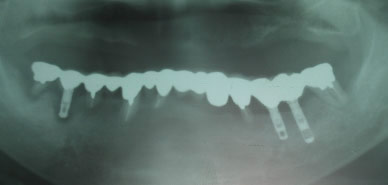

インプラントの画像(治療前)

インプラントの画像

インプラントのレントゲン画像(治療前)

インプラントのレントゲン撮影画像

7本がご自身の歯で、3本インプラントをしてありますが、1本のインプラントのまわりの骨がなくなっており、6本の自分の歯が歯周病で、やはり骨が吸収されております。すべての歯が連結されているため、このようなケースで再治療となりますと、すべての歯を撤去となり、治療費も大変です。

歯周病の歯はどのようにしても時間的に悪化していくことが多いです。